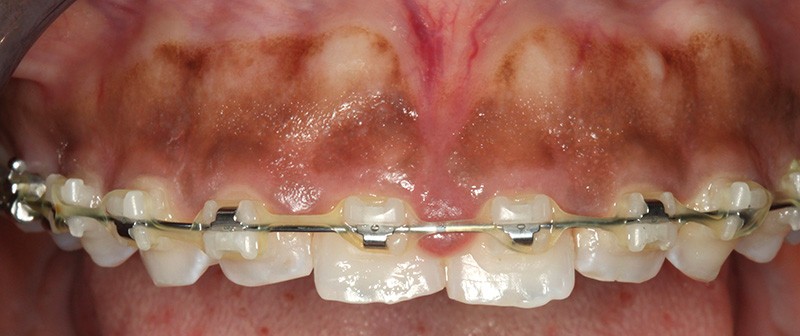

La gingivectomie du cadran 14-24 est programmée avec une prémédication de paracétamol (2 g/j péri-opératoire). L’anesthésie locale est suivie du pointage de la profondeur des poches (fig. 4) préfigurant le trait d’incision. L’incision à la lame froide à biseau externe (fig. 5) forme un angle de 45° avec la surface dentaire. Elle est festonnée en harmonie avec le contour existant des collets dentaires. Elle est complétée à la fraise rotative chirurgicale CeraTip® (KT314.016, Komet) (fig. 6). La section des fibres conjonctives circonférentielles est réalisée aux ciseaux d’Orban, et le bandeau de gencive est délicatement éliminé aux ciseaux de Kirkland n° 15/16. Le tissu de granulation et le tartre résiduel sont éliminés avant un rinçage à l’aide d’un mélange de peroxyde d’hydrogène à 3 % et de povidone…